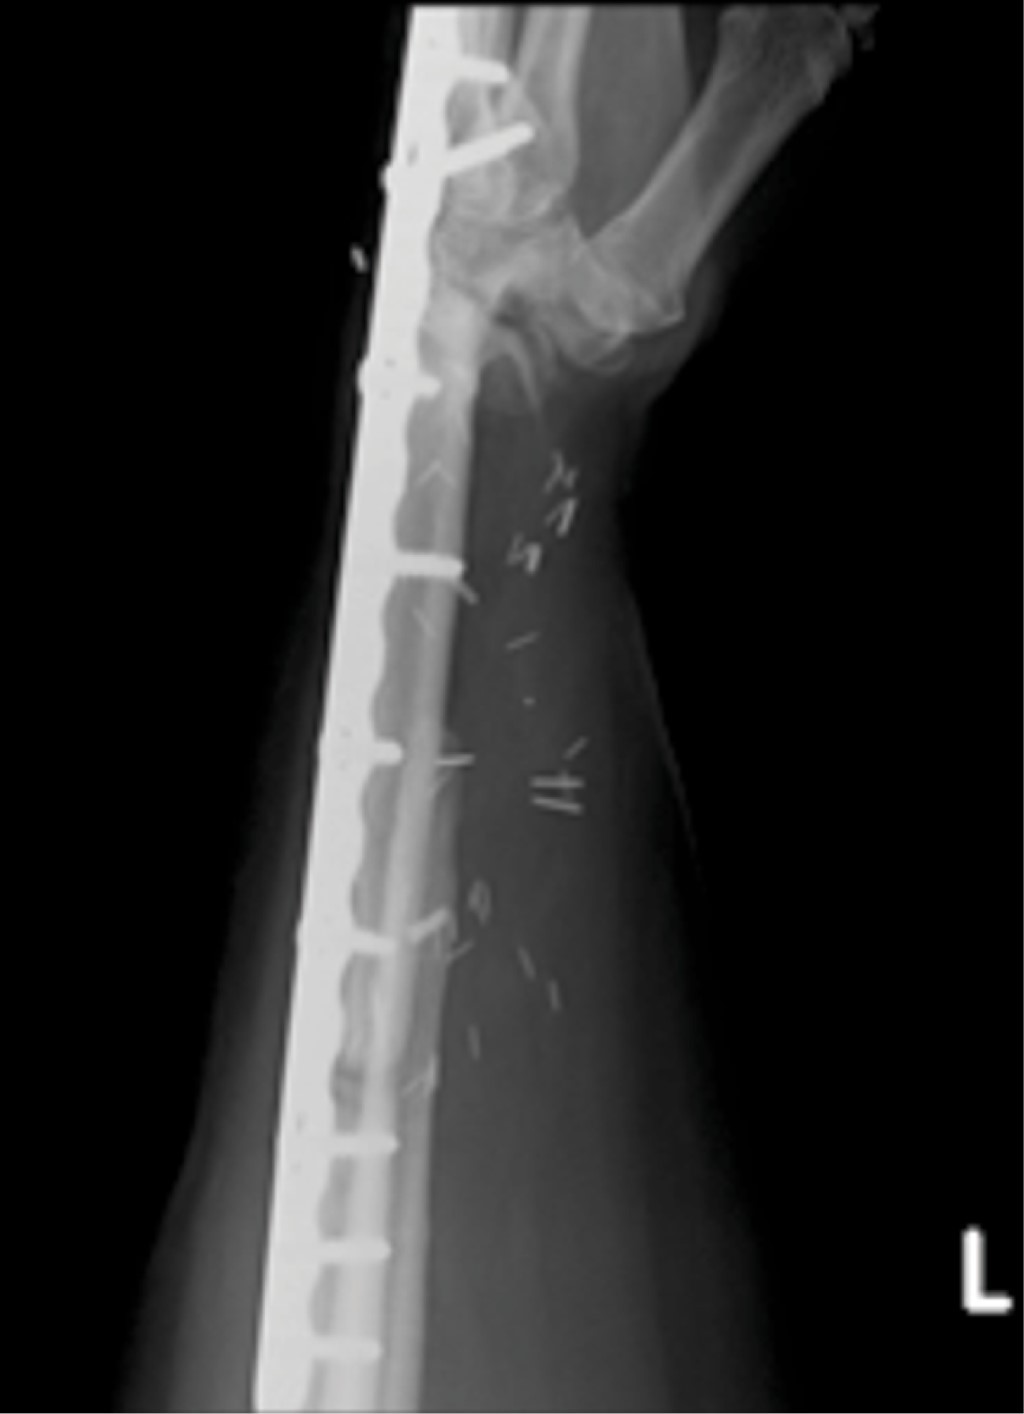

Presentamos el caso de una mujer de 45 años, sin antecedentes crónico degenerativos de importancia, que acude por presentar dolor en muñeca izquierda, con el antecedente de una fractura patológica de radio distal izquierdo en septiembre de 2018, tratada con reducción abierta y fijación interna con placa de radio distal volar y matriz ósea, actualmente consolidada. De inicio se realizó radiografía posteroanterior y lateral de la muñeca observando una lesión neoplásica en radio distal compatible con un tumor de células gigantes en un estadio III de la clasificación de Campanacci (Figura 1), se complementó el protocolo de estudio con tomografía de tórax descartando metástasis pulmonares y posteriormente se decidió como tratamiento la resección en bloque (Figura 2) (5 cm a la superficie articular proximal tanto de radio como de cúbito y se incluyó la fila proximal del carpo, todo a través de un abordaje dorsal) y reconstrucción inmediata con peroné vascularizado y artrodesis de muñeca con una placa de compresión bloqueada (Figura 3).

El seguimiento postoperatorio se llevó a cabo con controles radiográficos mensuales, se colocó una férula antebraquipalmar y se inició rehabilitación en la segunda semana. Sin embargo, al sexto mes persistía con dolor a nivel de la muñeca y el antebrazo, limitación funcional (pronación 90o, supinación -10o), debilidad (grip strength 50%, menor que el contralateral), con un puntaje DASH de 62.5, radiográficamente presentaba datos de no unión proximal y distalmente al peroné (Figura 4), misma que se decidió tratar de forma quirúrgica debido al tiempo de evolución.